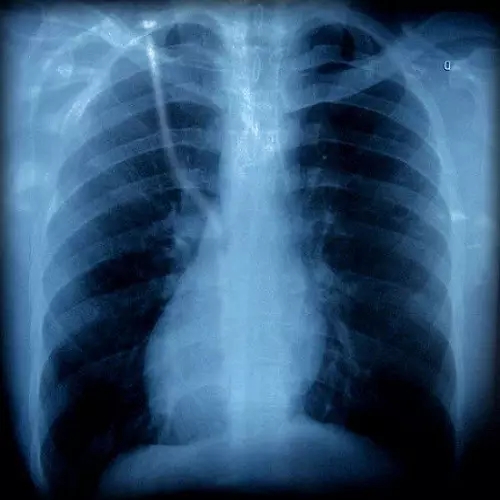

胸片有異

胸外科

咳嗽可以是由肺部腫瘤等疾病引起的,如果胸片或胸部CT上發(fā)現(xiàn)有可疑病變時(shí),應(yīng)該看看胸外科。一般,呼吸內(nèi)科大夫也會幫忙轉(zhuǎn)診的。